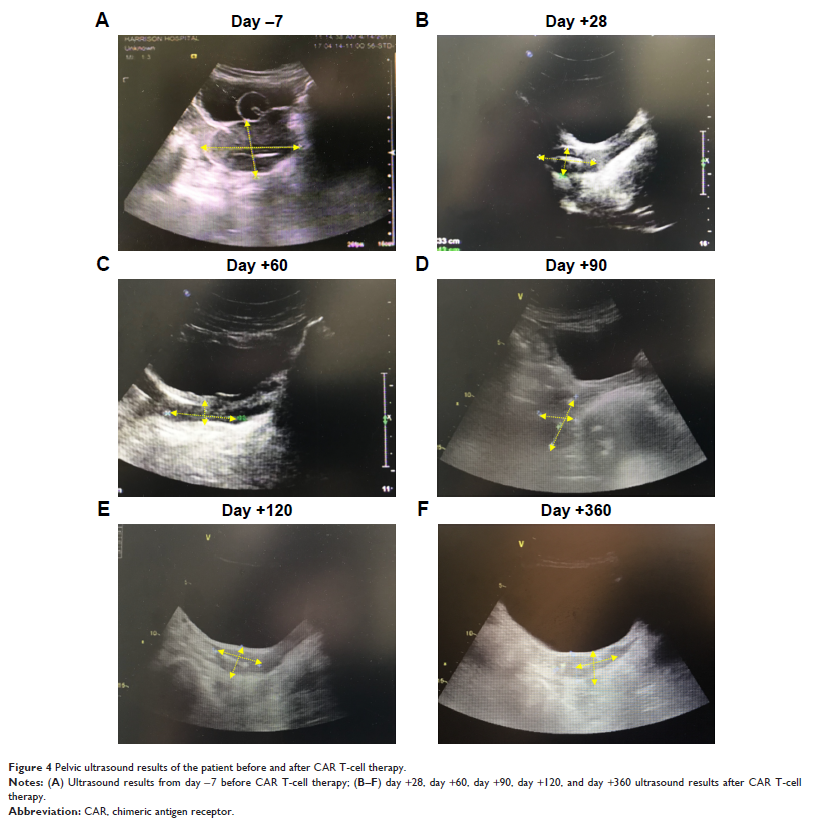

CAR T 细胞用于治疗异基因造血干细胞移植后急性淋巴细胞白血病髓外复发患者:一份病例报告